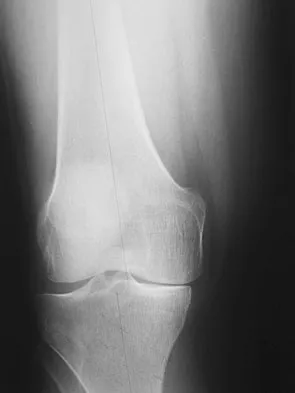

An 8-year-old girl was treated for a Salter-Harris type I fracture of the right distal femur 2 years ago. Examination reveals symmetric knee flexion, extension, and frontal alignment compared to the contralateral knee. She has 1-cm of shortening of the right femur. History reveals that she has always been in the 50th percentile for height, and her skeletal age matches her chronologic age. Radiographs are shown in Figure 9. What is the expected consequence at maturity?

Explanation

The child has a near complete central physeal arrest of the distal femur and worsening limb-length discrepancy will develop. She is growing at the average rate for the population. The distal femoral physis grows at a rate of roughly 9 mm per year. Girls finish their growth at approximately age 14 years. Thus, at maturity the left leg will be 6.4 cm longer than the right. An angular deformity has not developed at this point and her arrest is central; therefore, angular deformity is unlikely to develop in any plane. Little DG, Nigo L, Aiona MD: Deficiencies of current methods for the timing of epiphysiodesis. J Pediatr Orthop 1996;16:173-179.